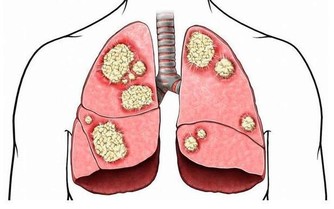

8 克林黴素:老年人慎用,必要時可用頭孢代替

在使用克林黴素時,其常見的不良反應,比如說過敏,包括過敏性休克、過敏樣反應、高熱、寒戰、喉頭水腫、呼吸困難等,或是腎臟功能損害的一些不良反應,嚴重的還會造成腎臟功能衰竭或耳功能損害。

因此,對於抗生素的選擇應十分謹慎。

而老年患者在就醫過程中,應將自己的病史、身體情況與醫生表述清楚,如有必要,可以採用頭孢類藥物進行抗細菌治療。